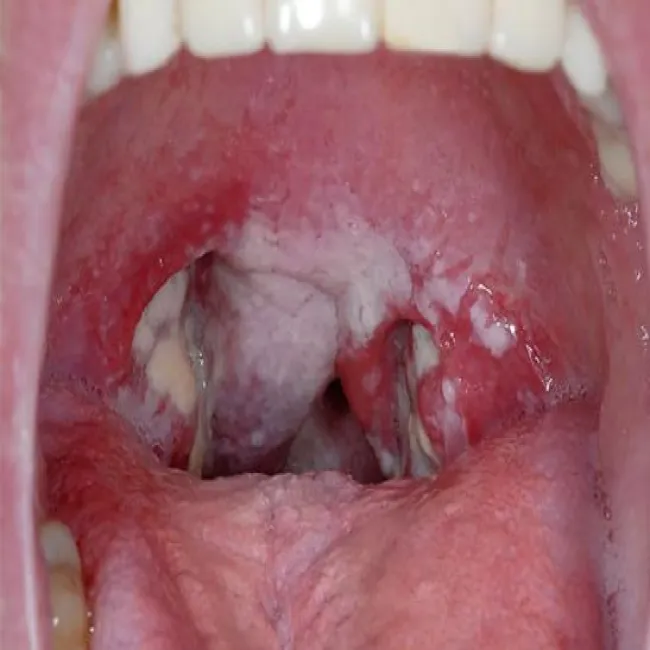

Objawy chlamydii w gardle

Chlamydia

Chlamydioza - chlamydia

Jama ustna